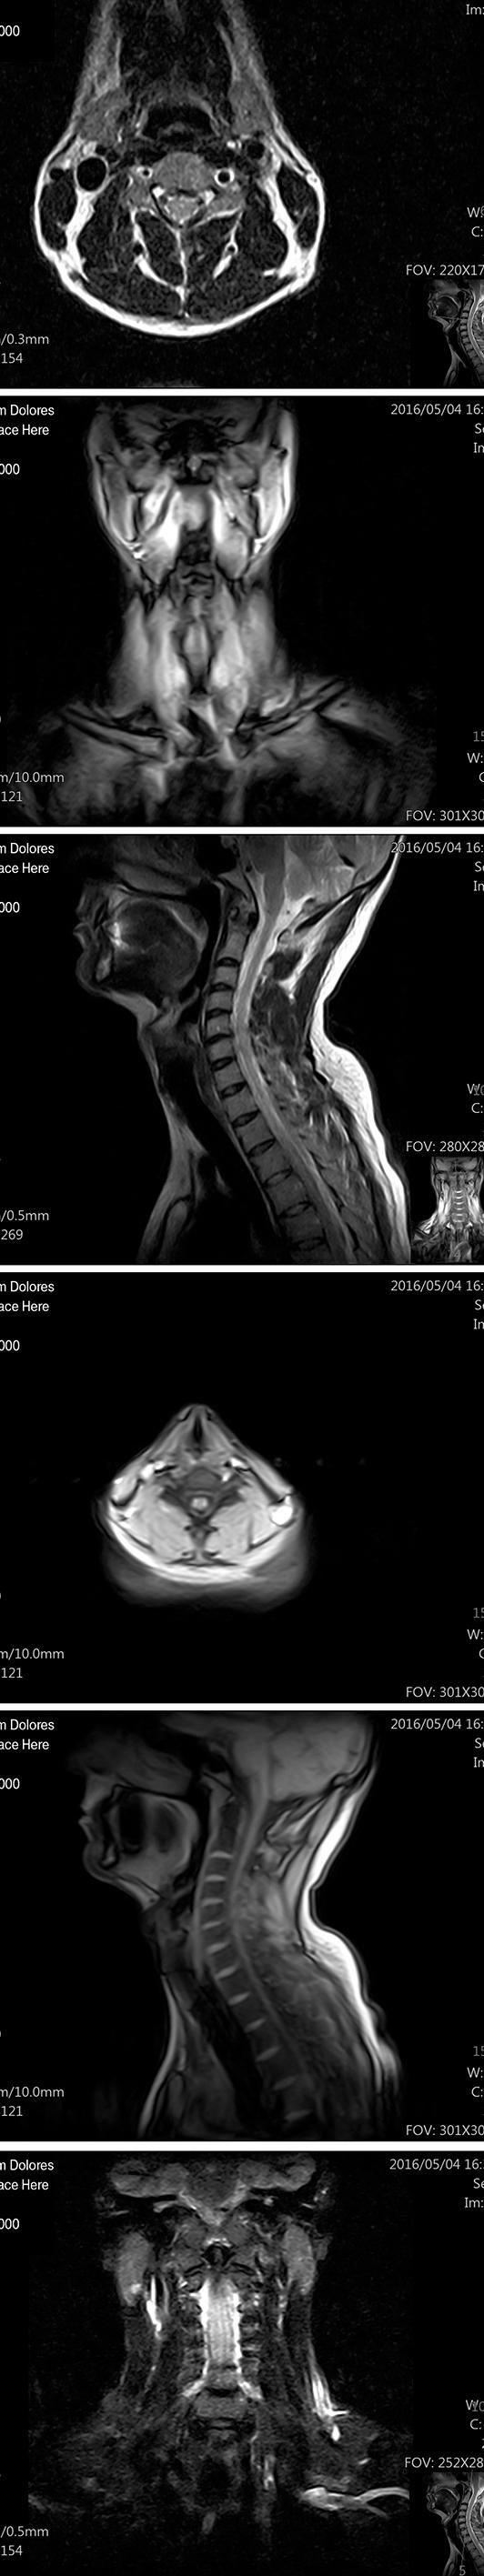

Researchers offer hypothesis for long COVID brain fog

Research tying brain inflammation believed to be triggered by COVID-19 infections to astrocyte function and glutamate homeostasis was the second most read article. In this study, French researchers suggested additional PET imaging with the use of translocator protein radiotracer for observing visual brain patterns and indexing the reactivity of astrocytes, starlike cells that play a key role in central nervous system functions. The research will continue.